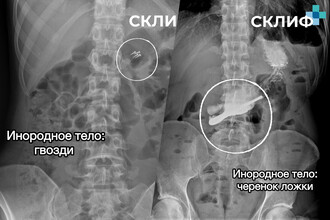

От наушников до гвоздей: врачи Склифа рассказали, что достали из пациентов в 2025 году